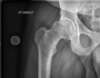

La radiologie confirme alors généralement l'importance de cette perte du cartilage articulaire (le cartilage n'est pas visible en radiologie), entraînant alors un rapprochement des structures osseuses entre elles (signe décrit comme un "pincement articulaire" sur les comptes rendus de radiologie). Des « becs de Perroquet » peuvent se former (ostéophytes) : ils témoignent d’une souffrance articulaire d’évolution lente.